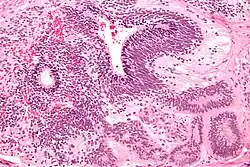

Dysgerminomas are comparable to testicular seminomas and account for approximately 32- 37% of all OGCTs.[1] They are particularly prominent in individuals with dysgenic gonads of 46, XY pure gonadal dysgenesis patients.[1] Based on gross examinations, dysgerminomas are characterized by having a ‘solid, lobulated, tan, flesh-like gross appearance with a smooth surface'.[1] Microscopically, the cellular structure is distinguished by a round-ovoid shape containing ample eosinophilic cytoplasm and an irregularly shaped nuclei.[1] The uniformly positioned cells are separated through the fibrous strands and lymphocytic infiltration is commonly observed.[4]